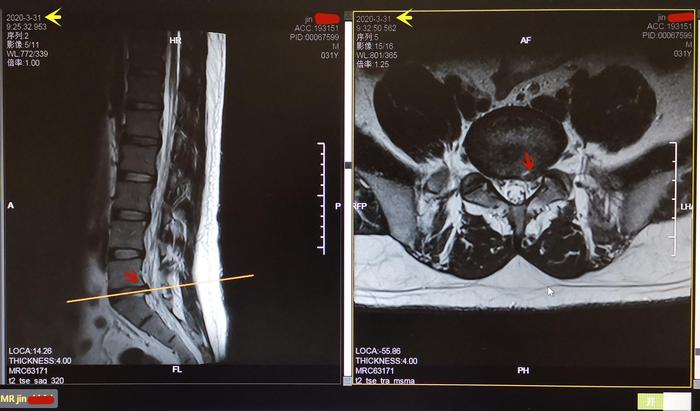

2. Jin先生,31岁,2年前反复发作左腰臀部疼痛1年余,多种治疗效果不佳,20202月急性发作后,疼痛严重,不能站立、行走,卧床3周余,左腰臀部压痛明显。腰椎核磁共振:L5-S1椎间盘左侧突出:图4。经过功能训练复健腰痛消失,维持训练避免了复发加重,能够完成繁重的日常学习工作。图5

4. Jin先生2020331日腰椎L5-S1间盘左侧突出(红箭头)